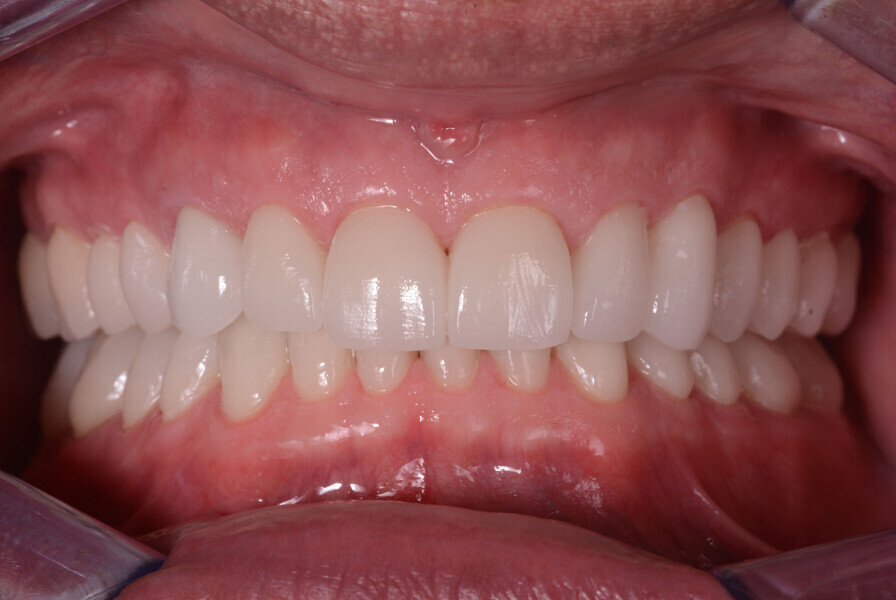

Fig. 13: Intraoral photographs after treatment.

Figs 14: Intraoral photographs after treatment.